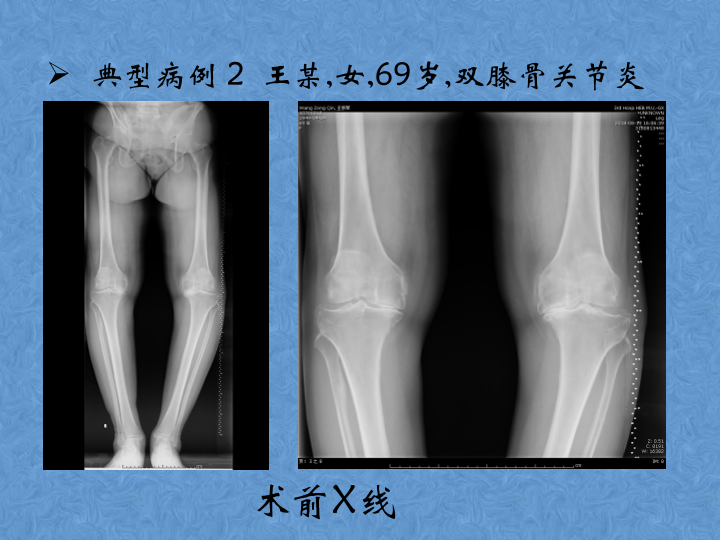

骨关节炎的阶梯治疗